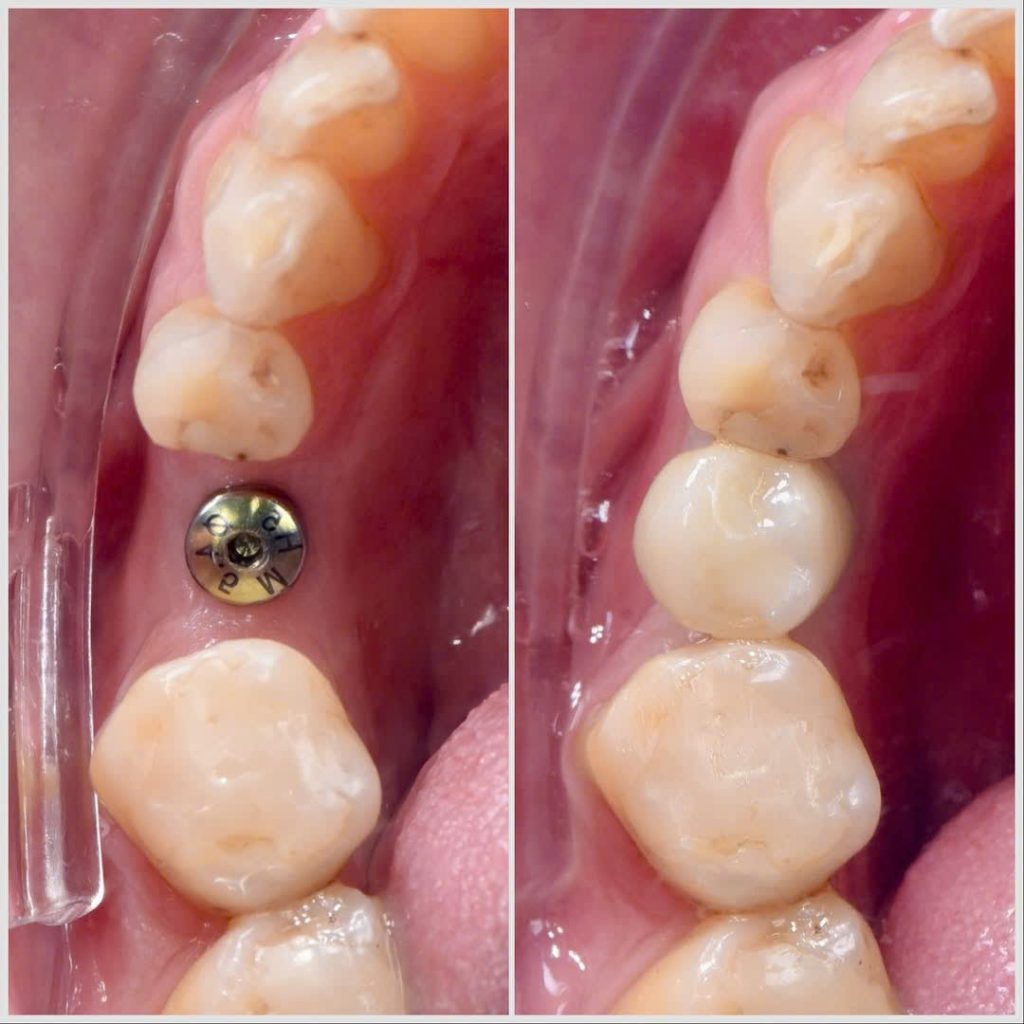

Mất 1 răng

Bác sĩ sẽ cấy 1 trụ implant theo nguyên tắc mất răng chỗ nào cấy Implant chỗ đó